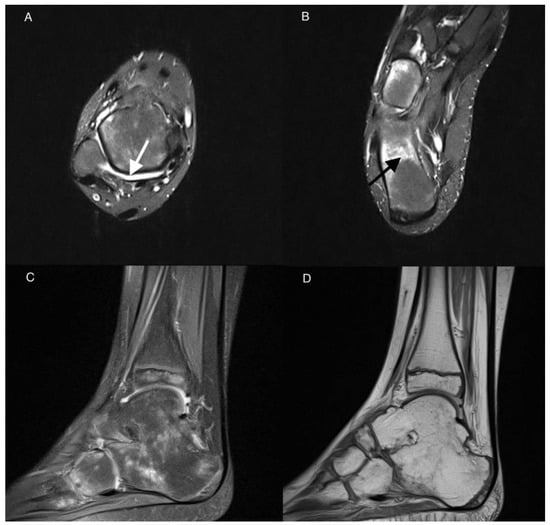

| 24 | Bursitis | |||

| 0 | 20 (91%) | 22 (100%) | 0.469 | |

| 1 | 2 (9%) | 0 (0%) | ||

| 28 | Chondromalacia | |||

| 29 | Joints space narrowing | |||